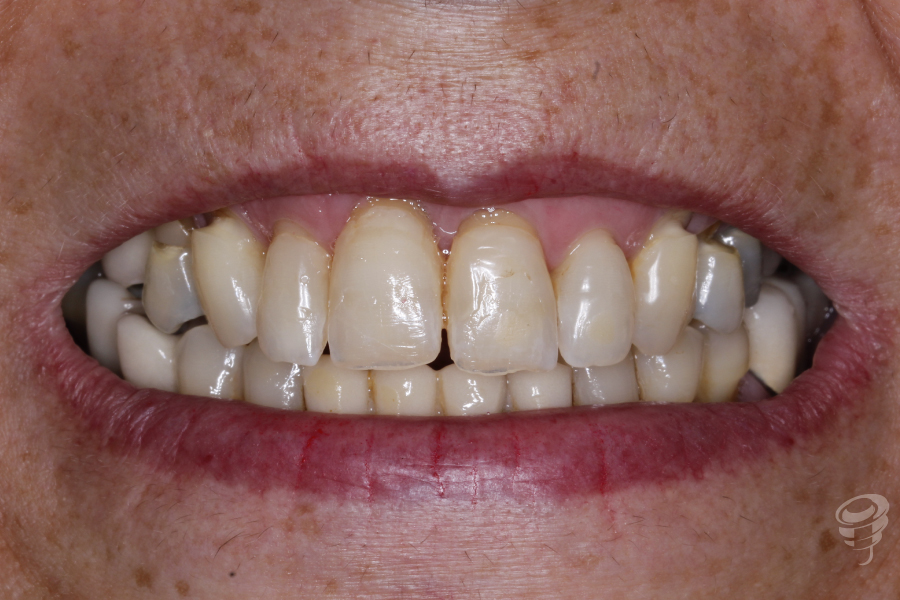

Podemos notar la pérdida de soporte periodontal que hay en el 11 y 21 y una descompensación asimétrica de los márgenes gingivales. Además, mordida abierta anterior y posterior derecha, mordida cruzada posterior bilateral, guías caninas ausentes. Un precario ajuste oclusal y bruxista. Podemos observar notables signos de abfracción en los cuellos 14, 13, 23, 24 y 25.

Figura 1

Figura 2

Figura 3

Figura 4